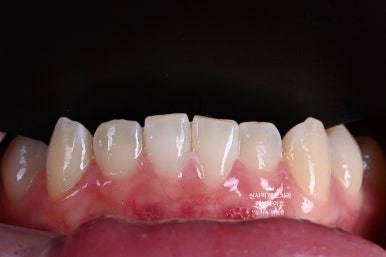

저희 김경호 세라미스트의 솜씨가 돋보이는 사진.

저는 보자마자 감탄을 금치 못했었습니다.

단지 앞면만을 덮는 라미네이트로, 이렇게 정교하게 질감과 색상을 표현할 수 있다니...

더더구나 알록달록이라 표현했던 질감까지도 정밀하게 구현된 것이 기가막히더라구요.

솔직히 어느게 치아고 어느게 레브네이트인지 구별이 안되지 않나요?

다시 봐도 참 신퉁하다는 생각 뿐입니다. ㅎㅎ

이게 진짜 예술작품이구나.. 마스터피스구나~ 하는 생각이 들더라구요.